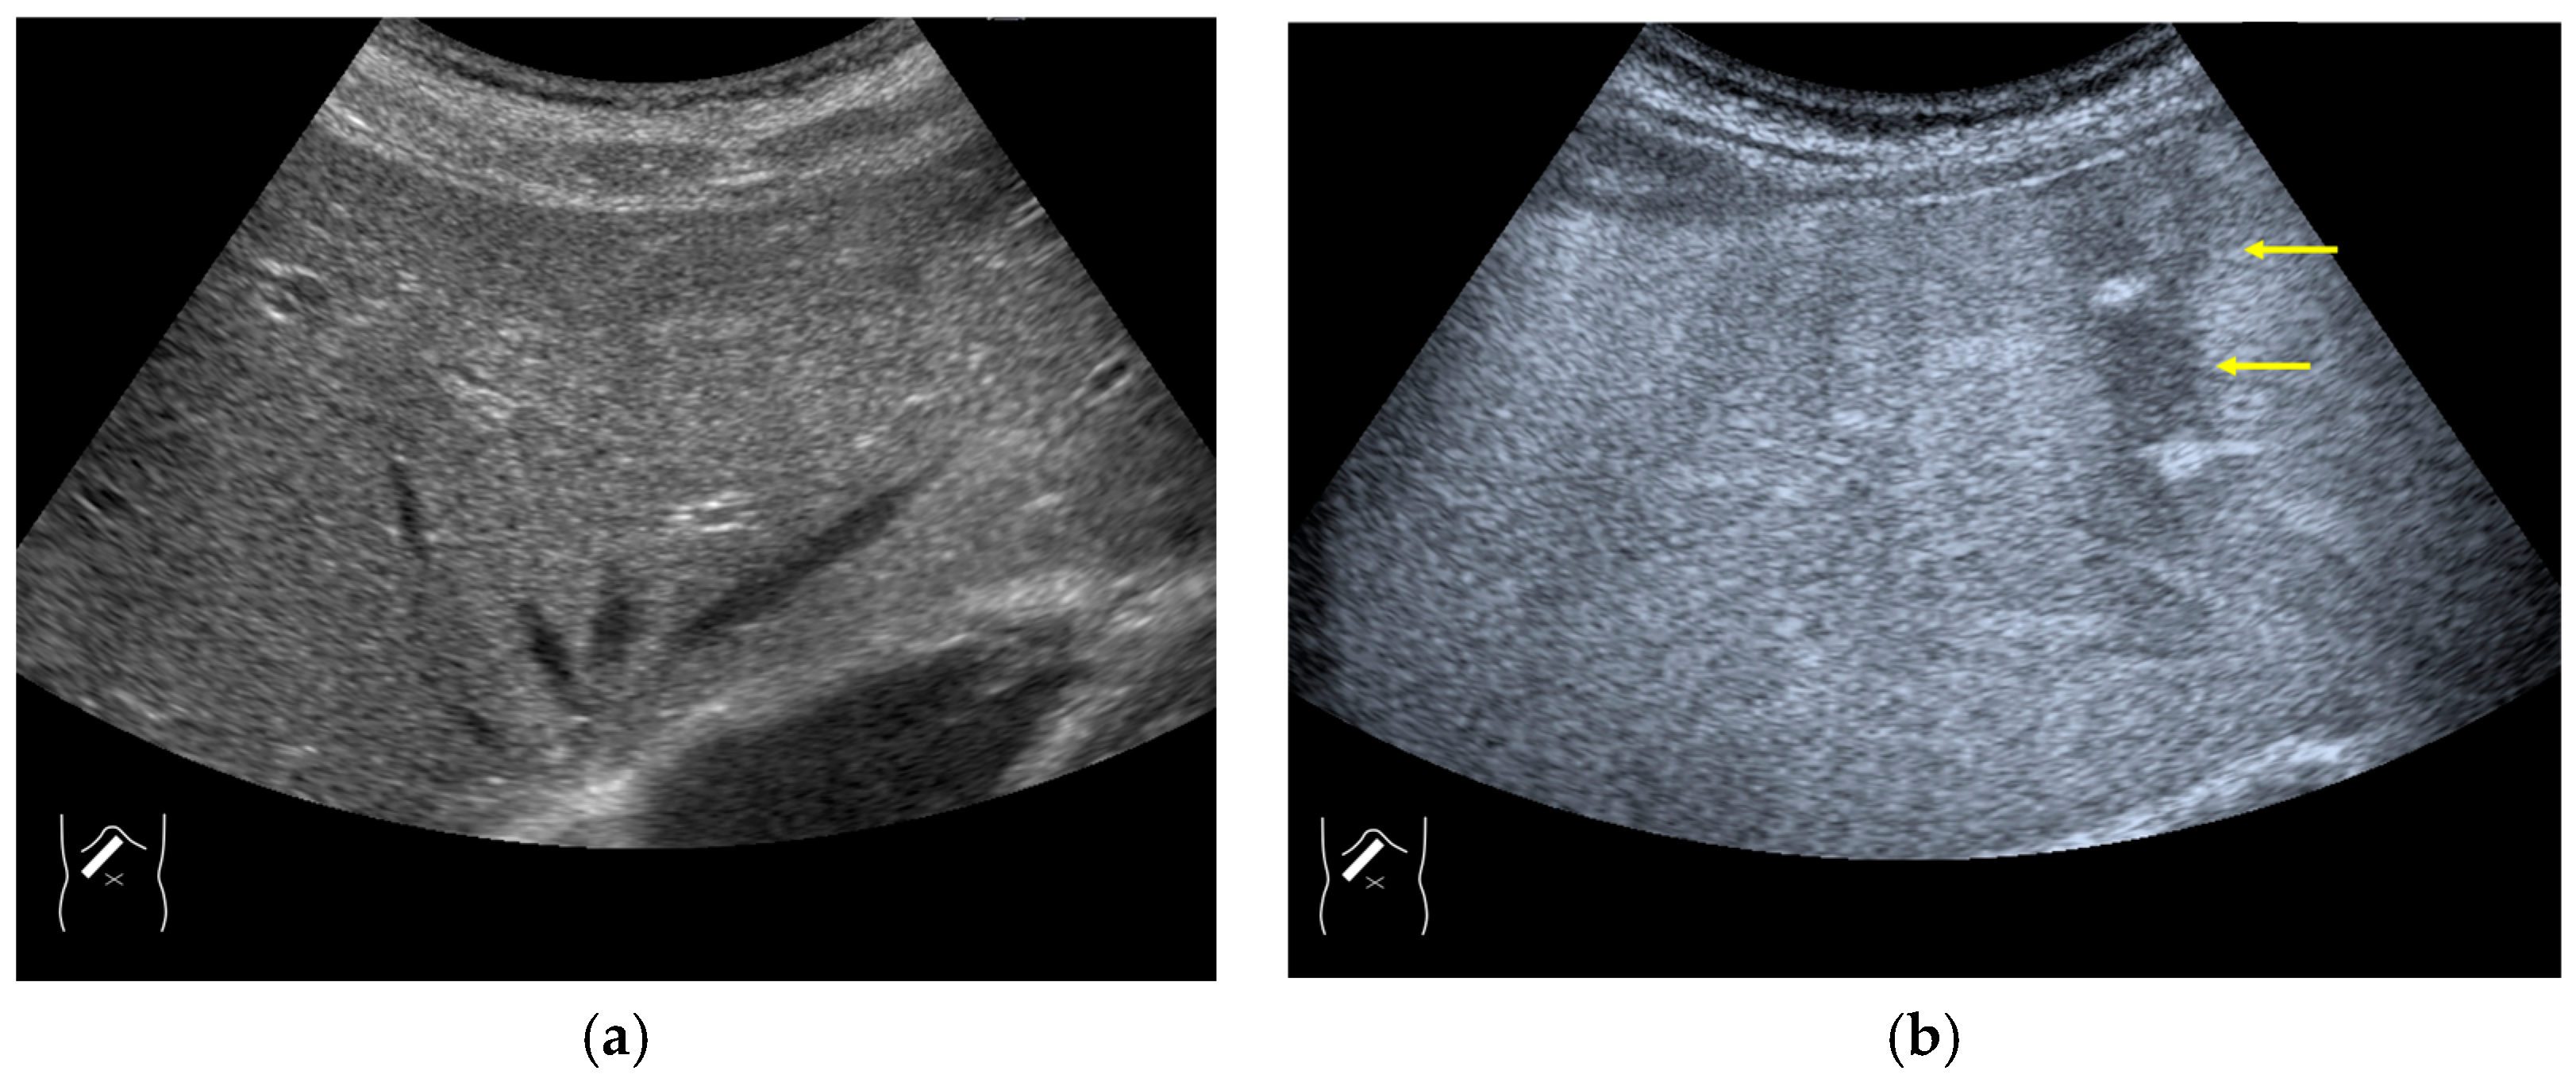

3.2.1. Microbubble Destruction Artifacts

Microbubble destruction occurs during daily CEUS examinations in all phases, even under the optimal settings. The most representative example is a microbubble destruction artifact seen at the hepatic surface (Figure 11). Thus, it is important to understand that inappropriately increased microbubble destruction occurs in the case of continuous CEUS examination, even under optimal settings. Bubble destruction artifacts cause a delicate diagnostic problem, especially when evaluating the degree of wash-out. Generally speaking, the degree of microbubble destruction differs from area to area depending on the blood flow velocity. We encounter this problem most frequently in hemangioma, where destroyed microbubbles are not quickly replaced in intrahemangioma sinusoids because of the low blood flow velocity within them [53], while destroyed microbubbles can be quickly replaced in the surrounding hepatic parenchyma (Figure 12). This phenomenon causes the important diagnostic problem of mimicking a malignant lesion. According to the CEUS LI-RADS 5) classification, the presence of wash-out in the later phase suggests the diagnosis of a malignant tumor in more than 90% of cases [2,11,12,13,14,15,16]. The simplest prevention strategy is the “re-injection” of a contrast medium [54], which enables us to observe the target lesion in all phases once more, from the arterial phase until the later phase, with intermediate scanning interruptions.

Figure 11.

Microbubble destruction artifact. (a) Gray-scale US of the liver surface shows no abnormality. (b) Although the M.I. of the examination is not very high, a long scanning time (approximately 15 s) causes an unintentional microbubble destruction artifact (arrows) at the hepatic surface.

Figure 12.

Manhole-like defect in hemangioma: (a) gray-scale US of the case (arrows: hemangioma); (b) CEUS shows a cotton wool appearance in the periphery of the lesion (arrows): (c) the lesion shows a complete defect in the lesion during observation (arrows); (d) a reasonable explanation of this phenomenon. In hemangioma, destroyed microbubbles are not quickly replaced because of the low blood flow velocity, mimicking a wash-out phenomenon.